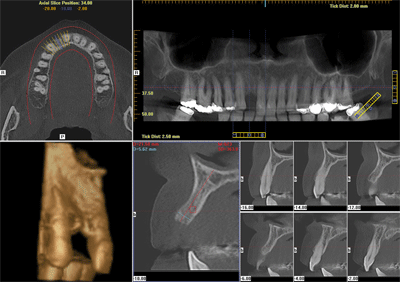

I-CAT Vision

I-CAT Vision é um software que gera imagens, onde integram módulos de visualização para ATM, implante e todos os cortes axiais, coronais e sagitais.